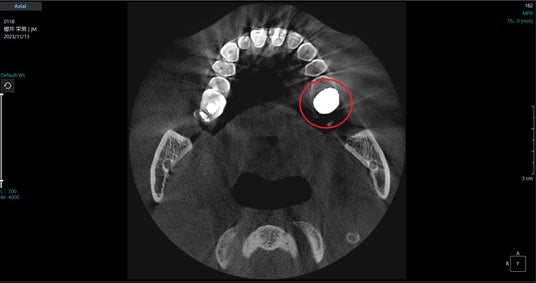

PanoACT 3D Upgradeシリーズは、パノラマやセファロの高画像品質だけでなく、CBCTの課題解決にも取り組んでおり、【図6ー2】に示したように、金属アーチファクト低減機能を開発しています。

アクシオン・ジャパンのアルゴリズムは、金属によって 生じた投影データ上の誤差を補正することで金属アーチファクトを低減する方法で、アーチファクトの発生要因によらずに投影データの補正を行うため、金属部が連続してフォトン不足が深刻な状態においても効果的に影響を低減できていると高評価を受けています。

【図6ー1】:PanoACT 3D Upgradeの金属アーチファクト低減機能例

【図6ー2】:PanoACT 3D Upgradeの金属アーチファクト低減機能例